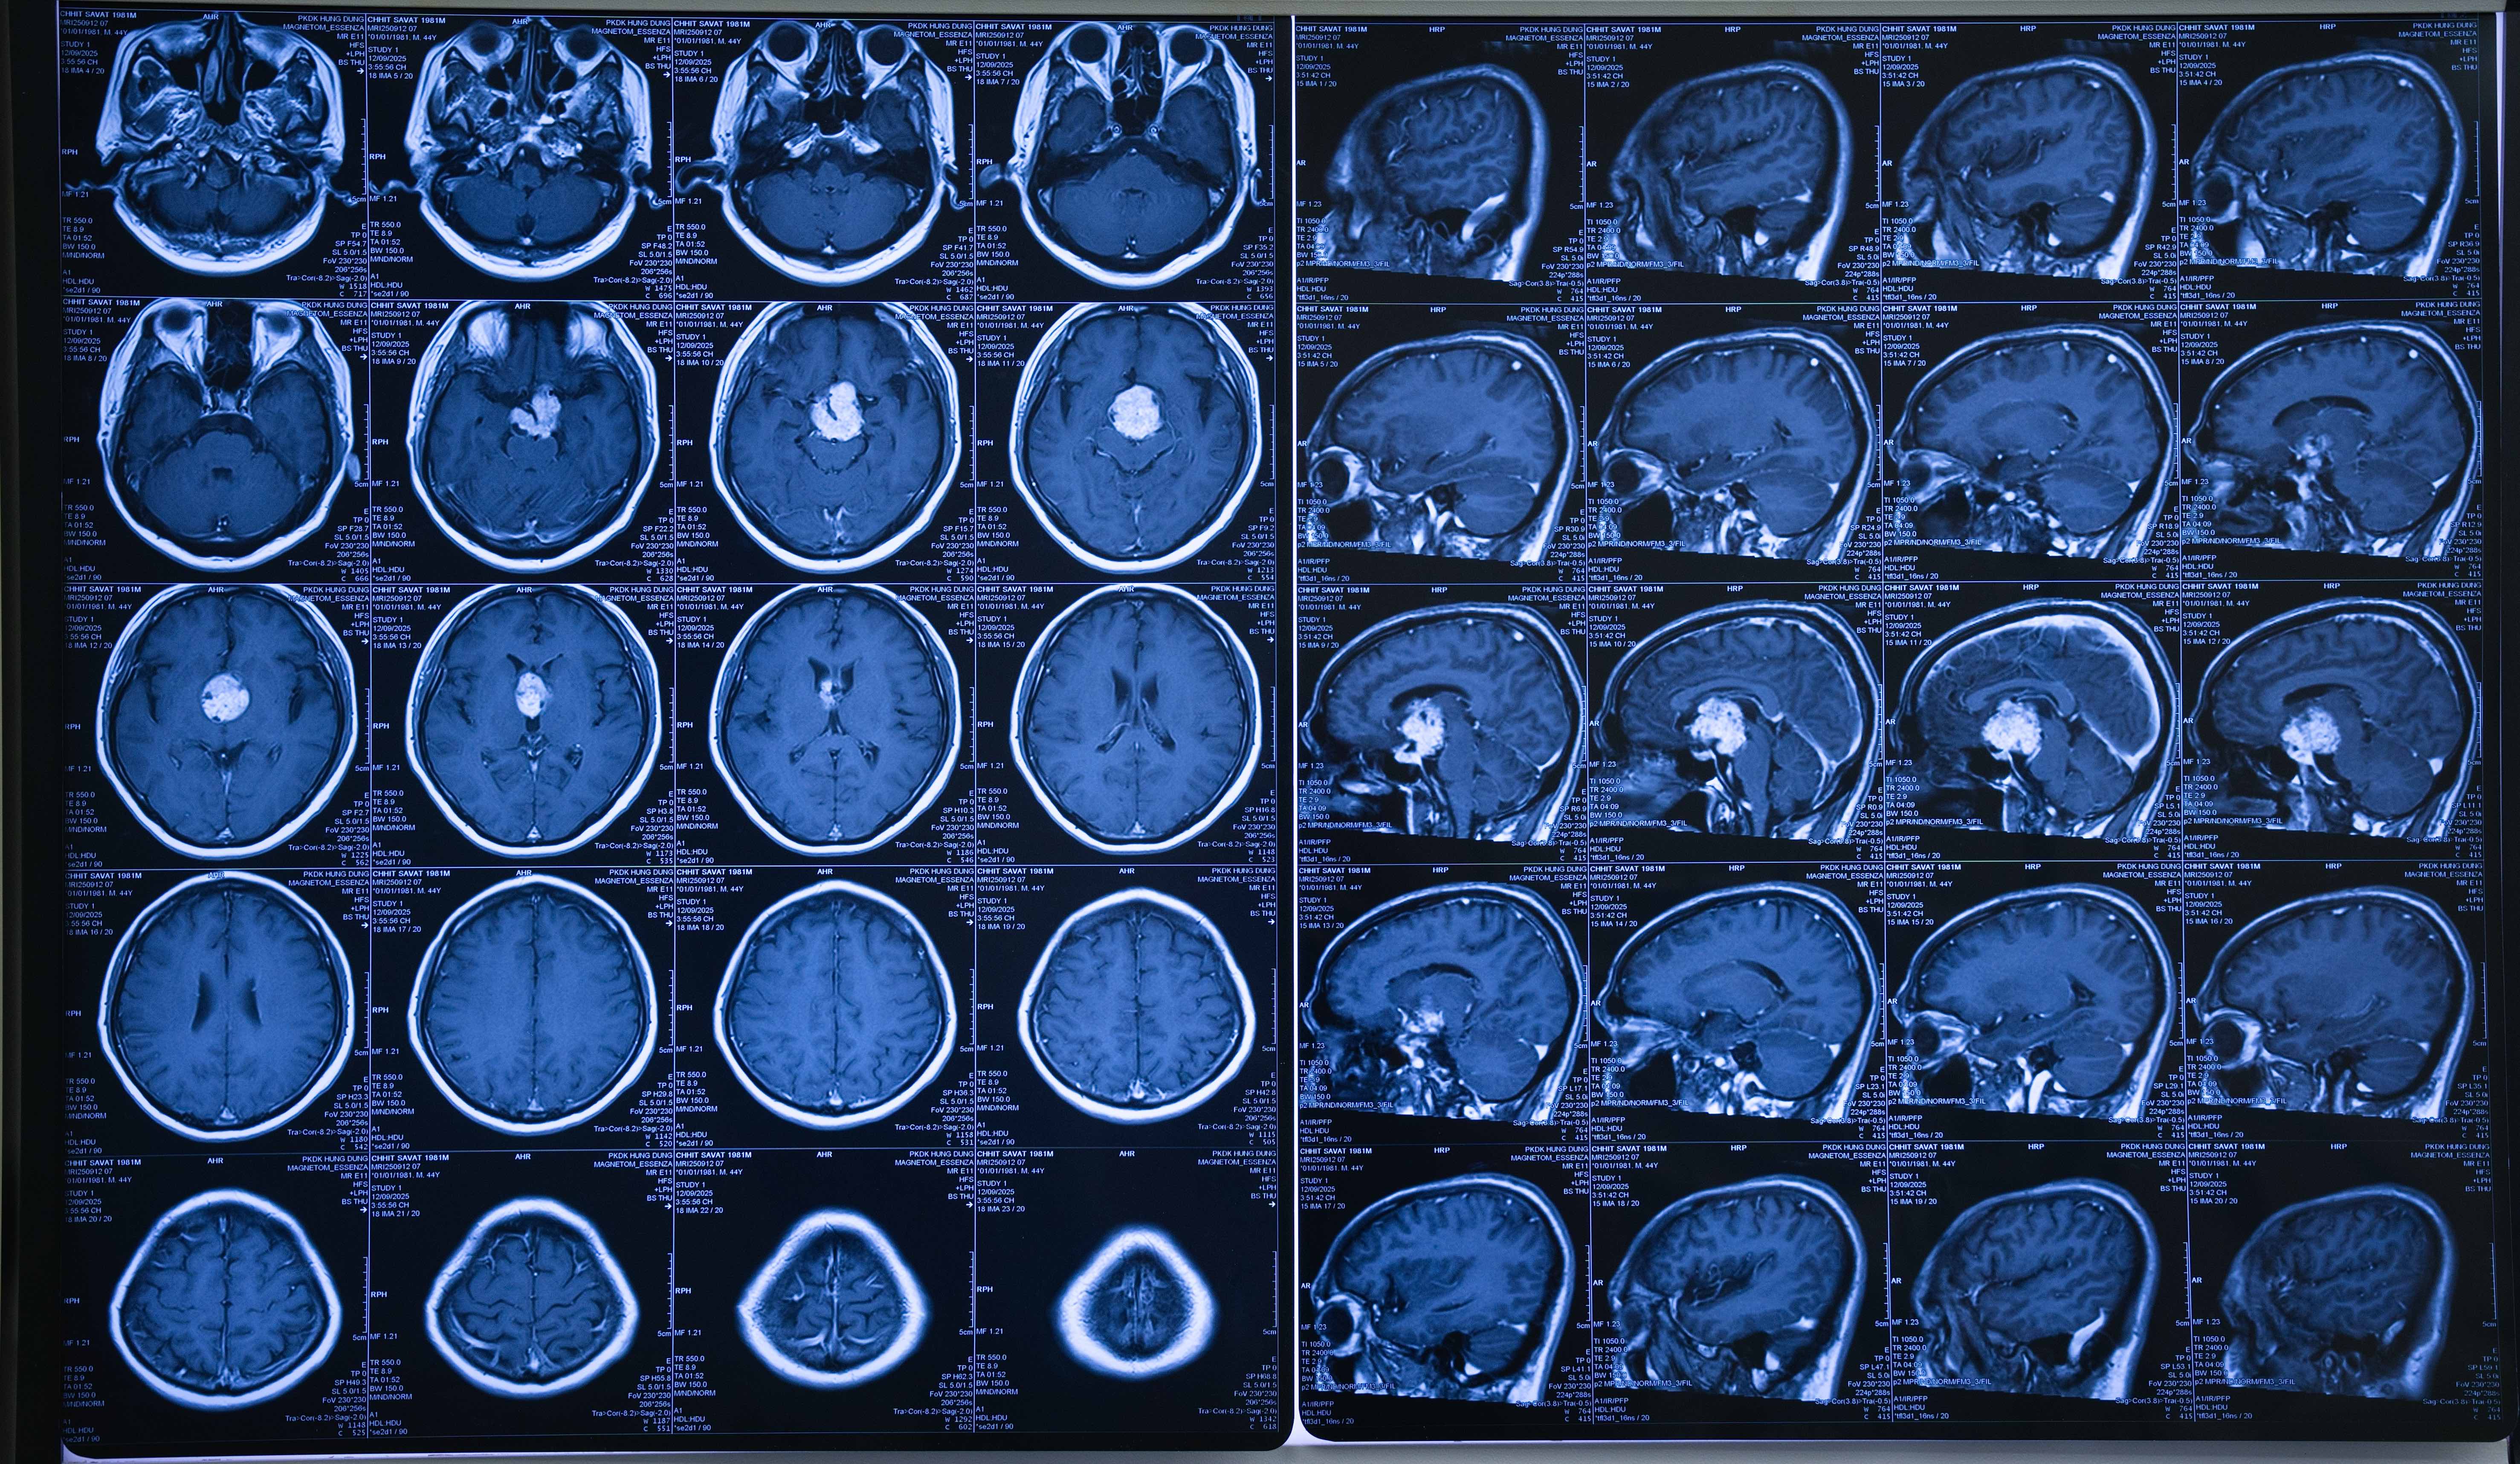

Hai tháng trước, bệnh nhân xuất hiện triệu chứng chóng mặt, nhức đầu, mắt trái gần như mất thị lực, mắt phải cũng suy giảm nghiêm trọng. Qua chẩn đoán hình ảnh hiện đại, các bác sĩ phát hiện khối u sọ hầu có kích thước lớn, chèn ép tuyến yên, cuống não, vùng hạ đồi và não thất ba. Với khối u xâm lấn, chèn ép các cấu trúc thần kinh và mạch máu quan trọng, trước đó nhiều bệnh viện từng từ chối phẫu thuật do mức độ phức tạp và rủi ro cao.

Theo BS.CK2 Đỗ Văn Long, chuyên khoa Ngoại Thần kinh - Cột sống, Bệnh viện Đa khoa Quốc tế Minh Anh, u sọ hầu kích thước lớn vẫn luôn là một thách thức trong điều trị. Phẫu thuật loại bỏ khối u đòi hỏi xác định chính xác từng cấu trúc thần kinh, mạch máu, đồng thời bóc tách tỉ mỉ dưới hệ thống kính hiển vi phóng đại.